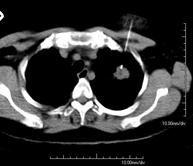

- TC Tórax

Prueba diagnóstica que consiste en obtener imágenes del tórax de alta definición anatómica (pulmones, corazón, mediastino, grandes vasos, caja torácica, etc.) mediante el empleo de un equipo de TC (Tomografía Computarizada). Dichas imágenes se estudian posteriormente en una estación de trabajo que permite reconstrucciones bidimendionales en diferentes planos del espacio y también reconstrucciones 3D (volumétricas). Algunos estudios requieren el empleo de contraste yodado para mejorar la definición de las imágenes. - Angio-TC Aorta torácica